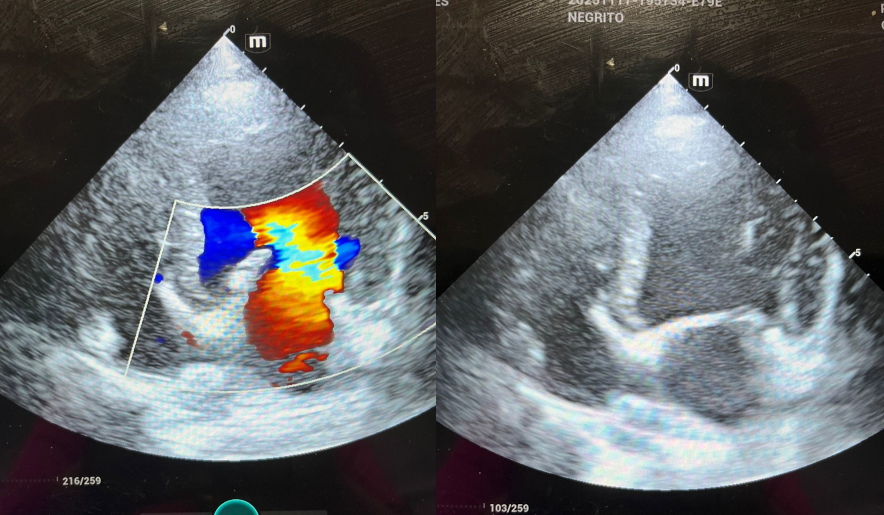

Estudio detallado del corazón con tecnología especializada. Realizamos ecocardiografías a domicilio o en la clínica, según disponibilidad de agenda y requerimientos del paciente.

Es una evaluación detallada del corazón mediante ultrasonido. Permite diagnosticar problemas cardíacos como soplos, insuficiencia cardíaca o enfermedades congénitas. Nuestro equipo portátil permite hacerlo en tu casa sin estrés para tu mascota.